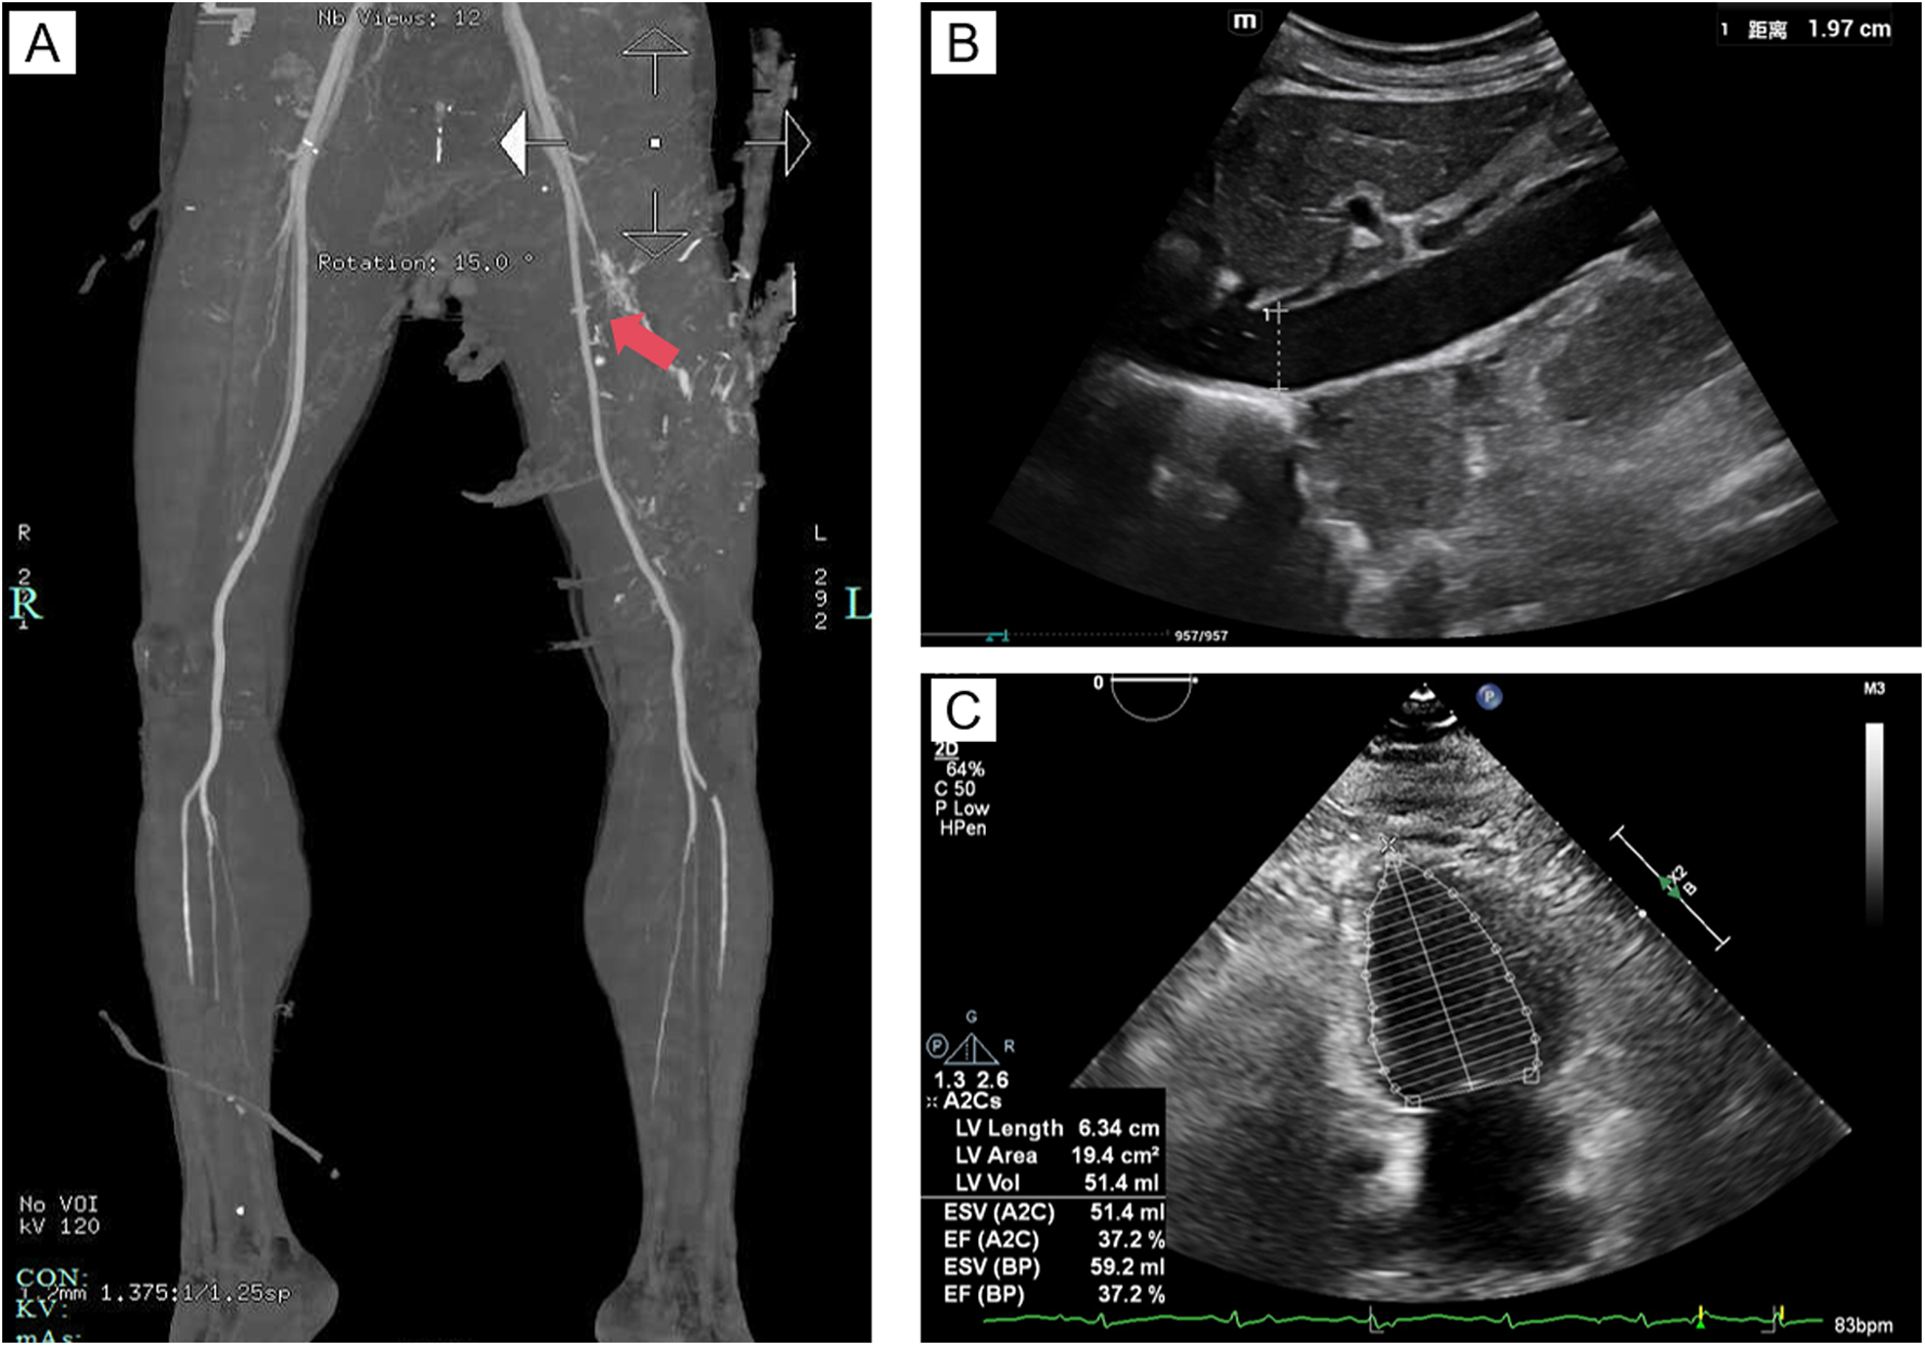

Figure 2

Imaging findings. (A) Contrast-enhanced CT of the lower extremities, with the red arrow indicating rupture and bleeding of the left femoral artery, with extravasation of contrast agent visible; (B) Ultrasound image of the inferior vena cava; (C) Echocardiographic image of the heart.

On the morning of the first day of admission, the patient was airlifted under the care of our medical transport team, comprising an attending physician and a nurse. The transport lasted only 35 min (a distance of 190 km), minimizing delays in initiating advanced treatment. Upon arrival at our hospital's emergency ICU, the patient remained hemodynamically unstable. Evaluation showed an inferior vena cava diameter of 1.97 cm (Figure 2B) and a left ventricular ejection fraction (EF) of 37.2% on echocardiography (Figure 2C), indicating post-cardiac arrest myocardial injury and cardiogenic shock. VA-ECMO was immediately initiated via femoral artery and vein cannulation on the contralateral side to the trauma to avoid complications at the injury site, along with mechanical ventilation and pharmacological support. Given the high risk of bleeding following vascular repair, anticoagulation was withheld during ECMO therapy. Coagulation function was closely monitored during ECMO support, and specific values are shown in Table 1.